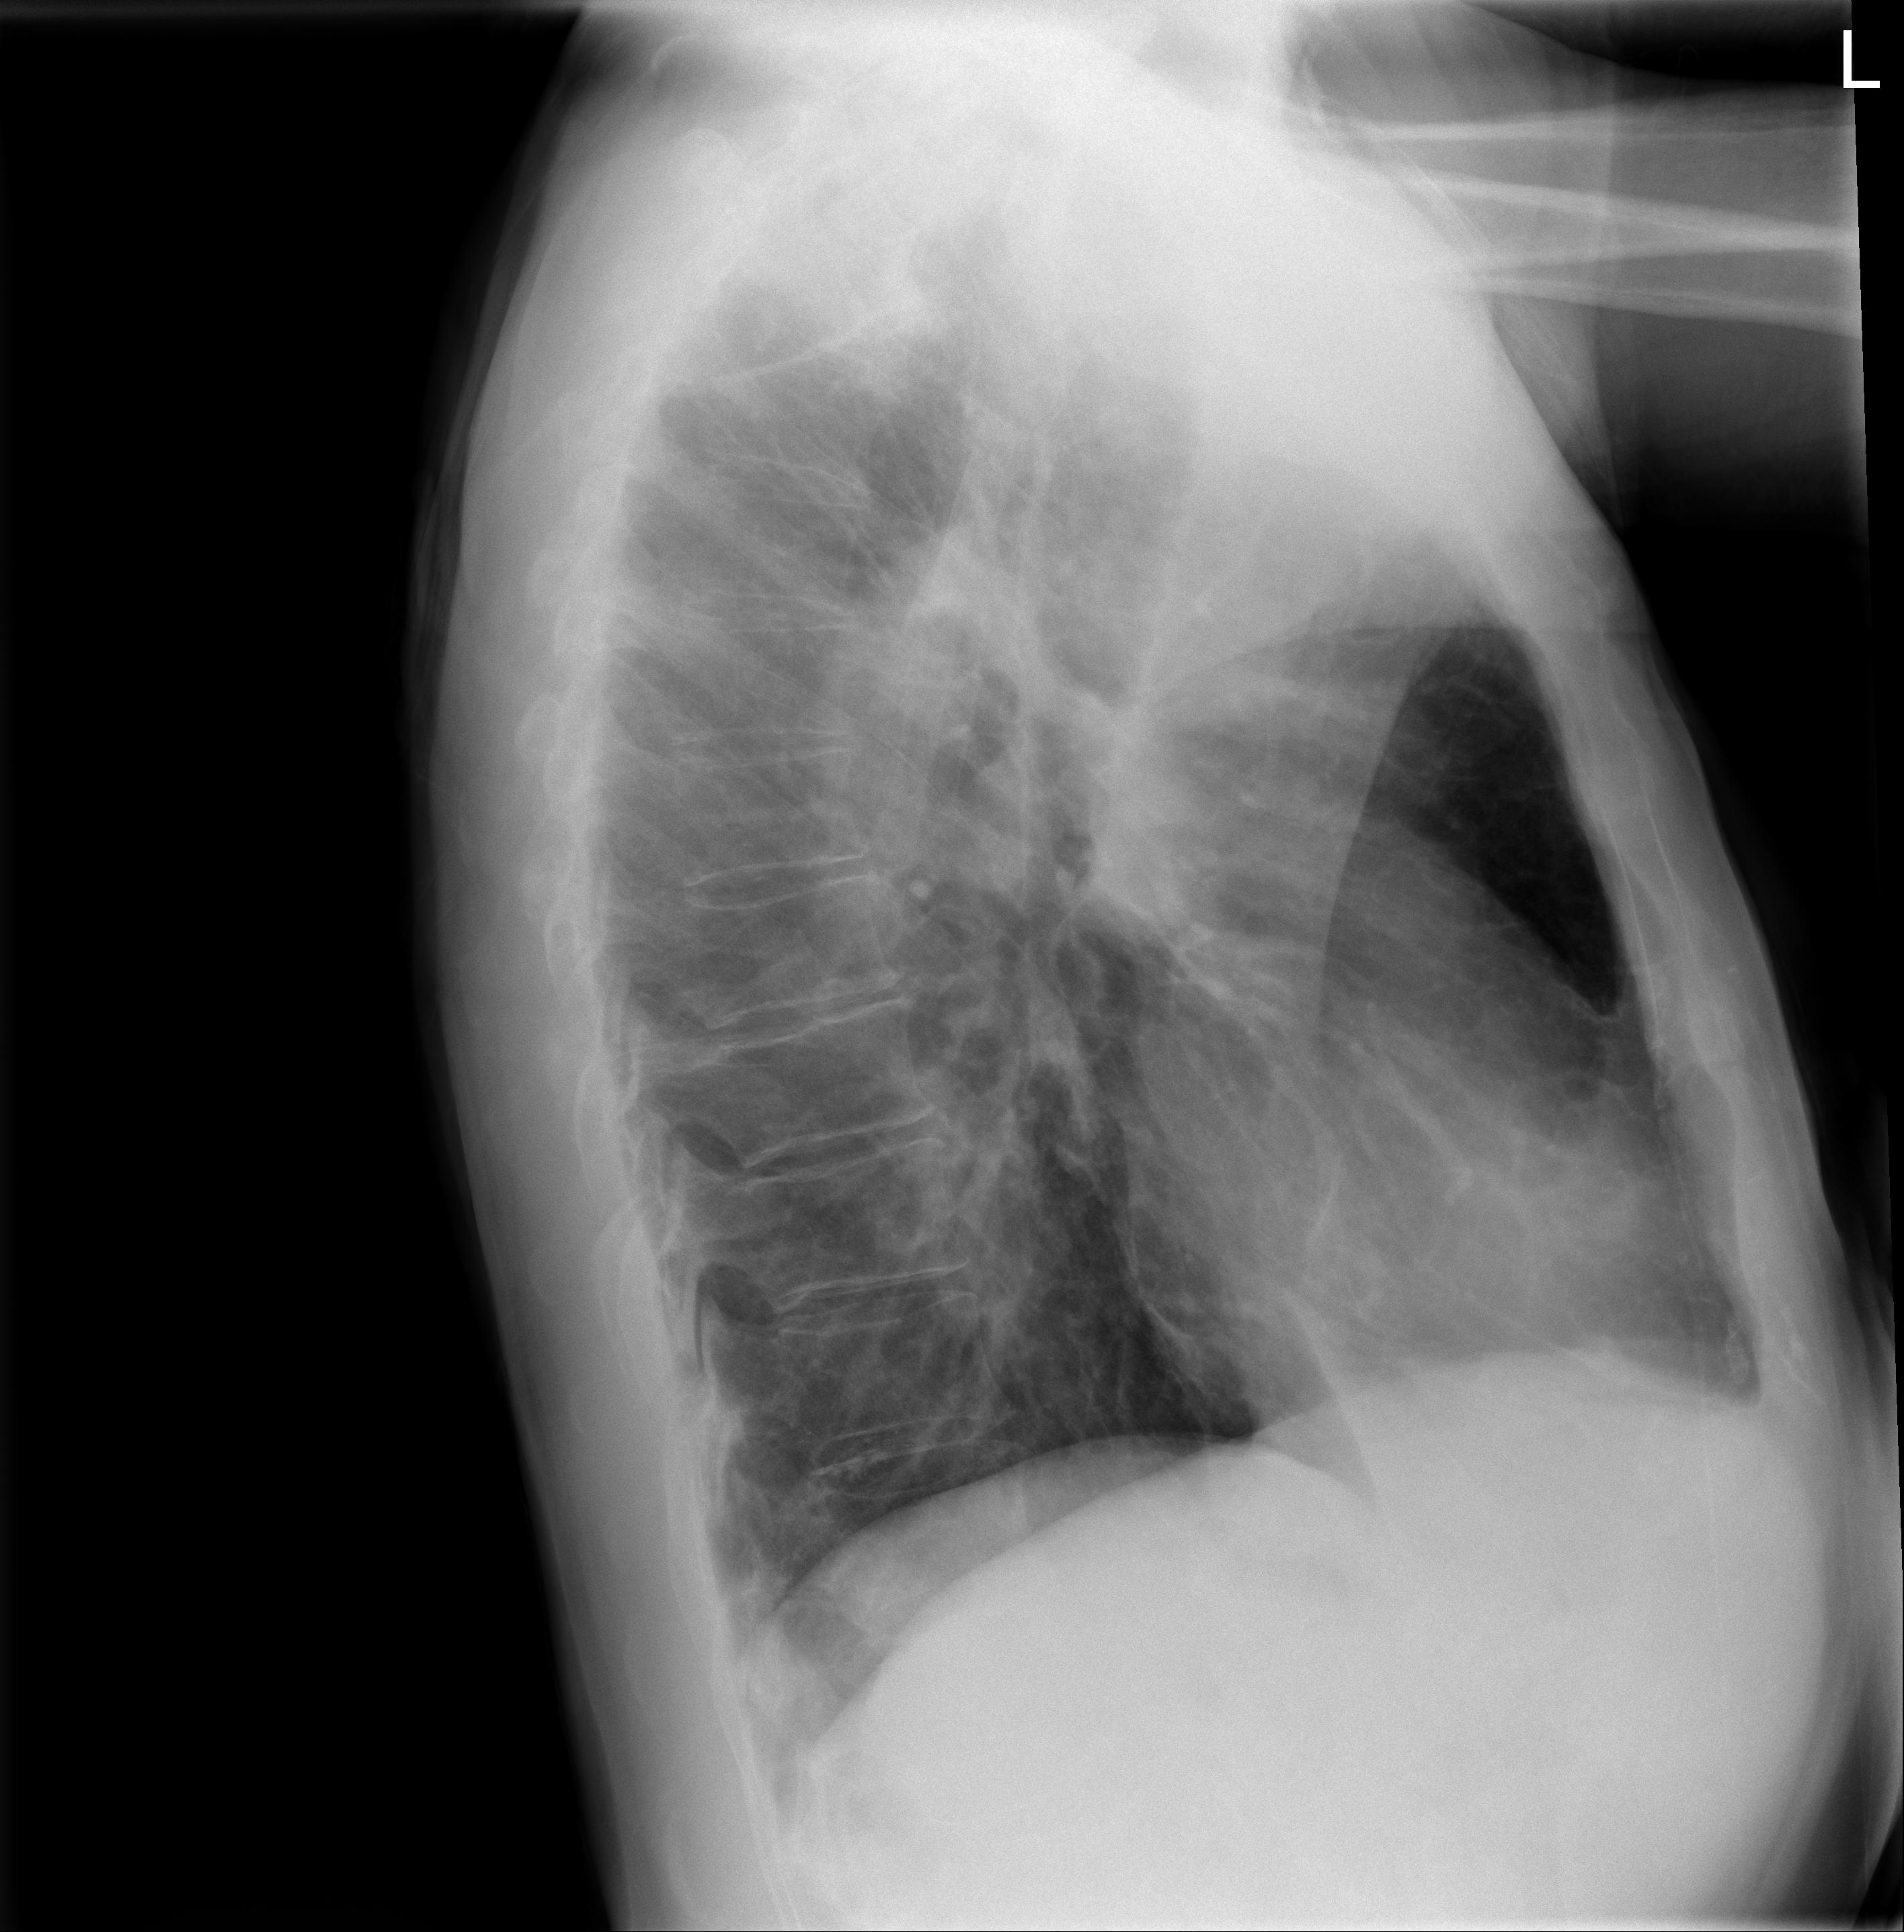

1 Tórax